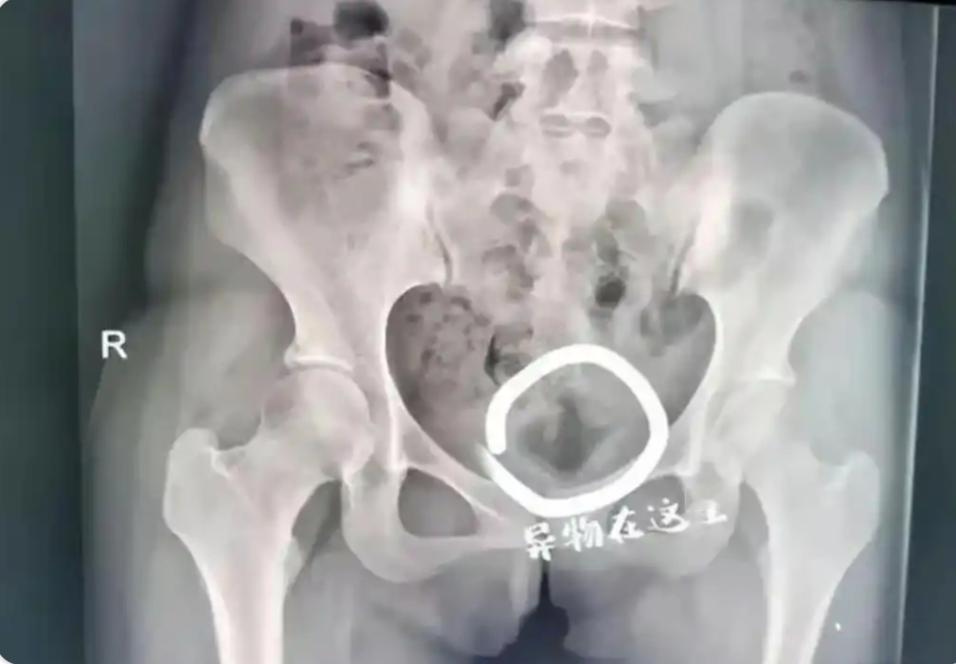

现在的大学生玩的可真花,凌晨三点妇科急诊来了一对大学生情侣,女孩19岁,来了就说自己下面疼,支支吾吾半天不好意思开口,男孩也低头不说话。 最后才搞清楚两人为了寻求刺激,让女孩把一个化妆品盖子塞了进去,取不出来,事后也不知道该怎么办,因为这事太过于丢人,愣是拖了一个月身体出现严重不舒服了才来就医,经过医生的检查,通过手术这个瓶盖最终被取了出来。 不得不说,年轻人玩的可真花呀,19岁成年人是恋爱自由,但这种行为显然已经超越了常人的理解,一些女孩为了迎合男友的好奇心,不惜牺牲自己的身体,最终的结果可能会让她们后悔一生。 这个事件也警示我们,必须建立正确的恋爱观,不然一旦出事败露,会引来大众的嘲笑,身体上也会造成巨大的伤害。